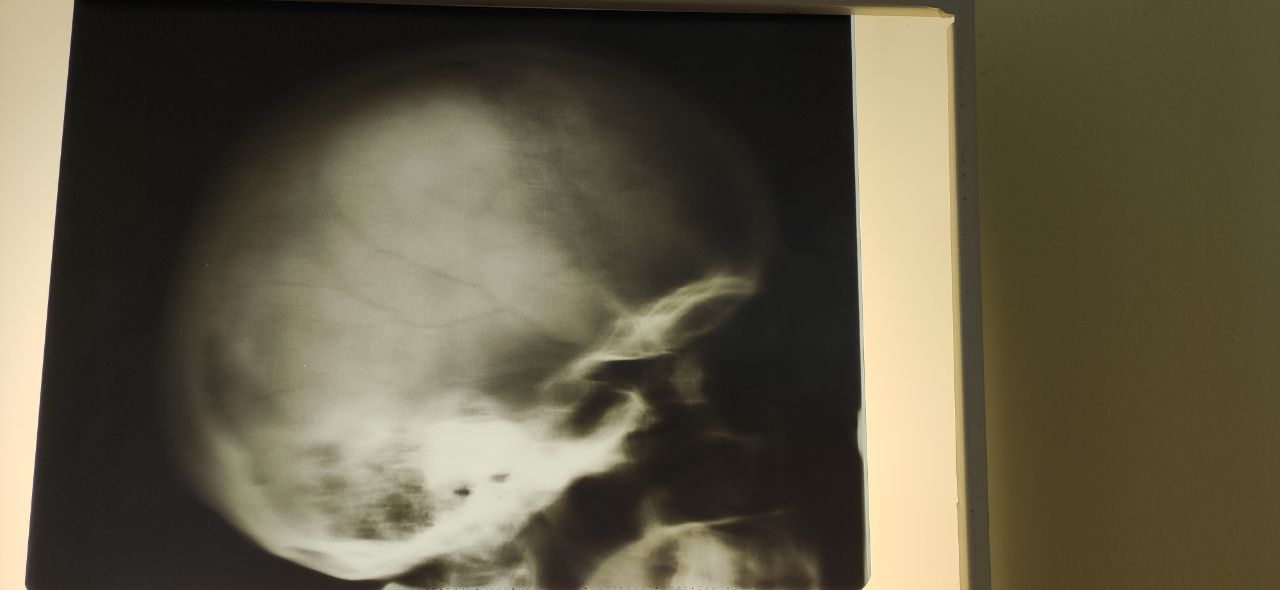

Женщина, 60лет. В анамнезе рак молочной железы.  Череп уплотнен? Мтс?

Плохого качества фото

Принесли такой снимок после выходных

Само фото плохое

Пусть ищут кт, за снимки ничего не скажу, качество неочень